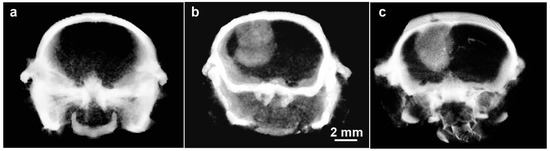

Cancers stimulate new blood vessel formation to support growth, and this leaky endothelium can accumulate NPs. An example of a glioma imaged with Niodx is shown in Figure 10.

Figure 10. MicroCT images of orthotopic gliomas growing in brains of athymic mice. (a) Before Niodx injection; (b) same mouse 24 h after intravenous injection (Niodx, 3.5 g iodine/kg); (c) Different mouse but taken 3 days after IV Niodx injection. X-ray source was 70 kVp.

The tumor to non-tumor ratio was measured to be ~20:1. It was also found that excellent tumor imaging remained after 3 days (Figure 10c), and likely longer (not tested). Such high resolution tumor painting could be used to accurately align and develop an optimal IMRT (intensity modulated radiotherapy) treatment plan. As the tumor painting is stable over days, additional contrast agent injections would not be needed for every RT fraction, especially for hypofractionated regimens.

It should be noted that the favorable tumor to non-tumor loading with Niodx in these glioma studies (human U87 in mice) was achieved without active targeting, presumably due to the Enhanced Permeability and Retention (EPR) effect [25]. Tumor blood vessels are, in many cases, more leaky towards nanoparticles. Some brain tumors have an intact, tight blood–brain barrier (BBB) blocking nanoparticle entry, but most GBM tumors in humans have an altered or disrupted BBB [26].